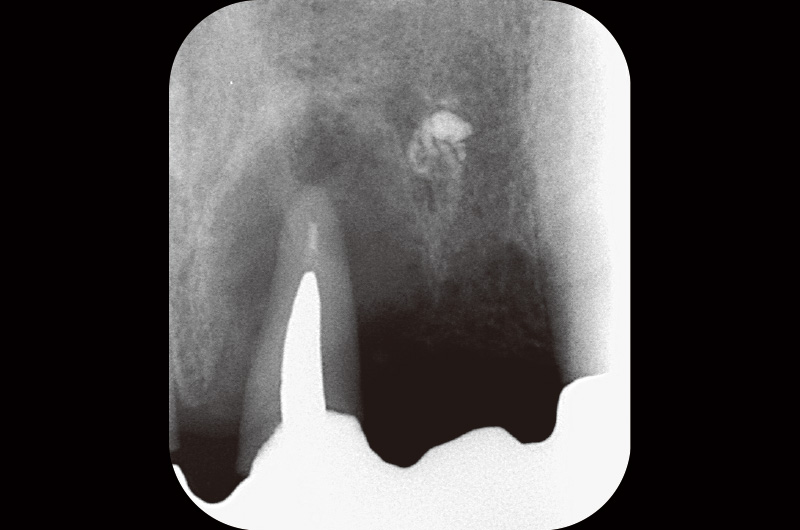

前歯は、②① ①2のロングスパンブリッジが装着されている。デンタルにて₁が歯根を取り囲むような透過像が確認された(図1)。

図1 21には、歯根を取り囲むような感染像を認める。22の根尖相当部にはGP様異物が確認できる。 -